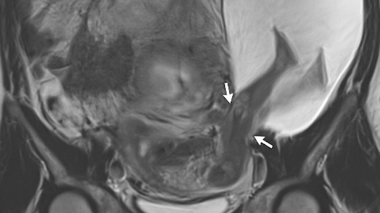

Lorsque le foetus se développe en partie hors de l'utérus

Source : Uterine Rupture with Protruded Legs in a Large Amniocele. P.E. Bouet, & C. Herondelle. NEJM, 22 déc. 2016. doi:10.1056/NEJMicm1603843